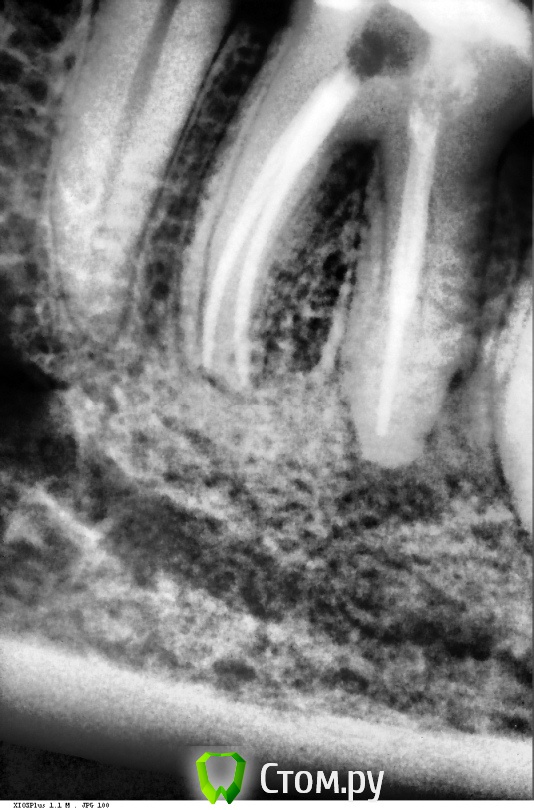

arimo Опубликовано 11 декабря, 2013 Поделиться Опубликовано 11 декабря, 2013 Добрый день. Помогите понять что дальше делать с зубом.Зуб- нижняя левая шестерка, депульпирован около 10 лет назад, периодически ныл, потом все проходило. В конце сентября начались сильные боли, неделю пришлось принимать кетанов. Врач вскрыл каналы (был гной), промыл, положил лекарство (какой то препарат кальция), через 2 недели запломбировал.Через 10 дней началась боли при надкусывании. Сейчас зуб сильно ноет, чувство распирания в десне, боль при легком касании.Вопросы:1. Имеет смысл повторно вскрывать каналы и класть лекарство?2. Если нет, имеет ли смысл делать резекцию корня и какие могут быть последствия? Ссылка на комментарий